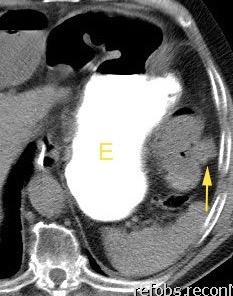

47. INTERPOSICIÓN CÓLICA DE CHILAIDITI

Interposición del colon entre hígado y diafragma

Más frecuente en pacientes con EPOC, cirrosis y ascitis

Incidencia.0,025%-0,28%.

Shinha T. Chilaiditi Syndrome. Intern Med. 2017

Vólvulo de flexura esplénica. Havenstrite KA. 1999

Hernia interna de colon transverso .hite JJ. 2002

Obstrucción cólica

Basile EJ et al. Chilaiditi Syndrome Presenting as Partial Colonic Obstruction. Cureus 2020